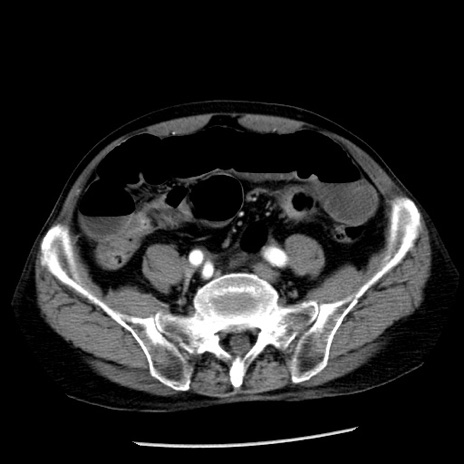

症例26(横断像)

【症例】80歳代男性

【主訴】嘔吐

【現病歴】昨晩2回嘔吐あり、今朝になっても嘔吐あり。来院。

【既往歴】胃潰瘍

【身体所見】意識清明、BT 37.6℃、BP 166/95mmHg、HR 100bpm、SpO2 97%、腹部:平坦・軟、腸蠕動音聴取良好、圧痛なし。

【データ】WBC 21900、CRP 1.46